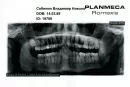

10 дней назад лечил зуб (крайний слева снизу, акт выполненных работ прикрепил). Дело в том, что болевые ощущения до сих пор не проходят (до лечения зуб не болел), а при легком надавливании на пломбу боль достаточно ощутимая, также отдает в ухо и в кость чуть ниже виска. После приема обезболивающего Кетофрил боль снимает.

Так как снимок после лечения отсутствует, сложно судить о качестве лечения. Но Вы должны понимать, что в случае даже качественного эндодонтического лечения может сохраняться болезненность и дискомфорта 2-4 недели. Для исключения осложнений стоит сообщить о симптомах лечащему врачу.